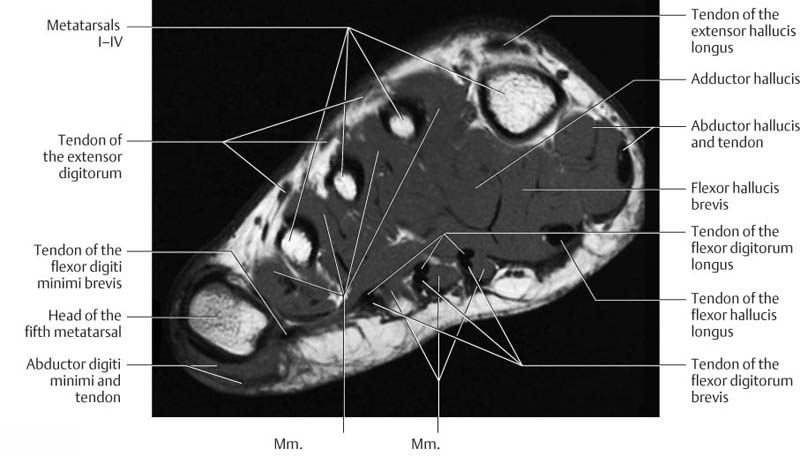

Forefoot Mri Anatomy

mavink.com

mavink.com

Ankle And Foot | Radiology Key

radiologykey.com

radiologykey.com

foot ankle axial radiology medial sole lateral radiologykey